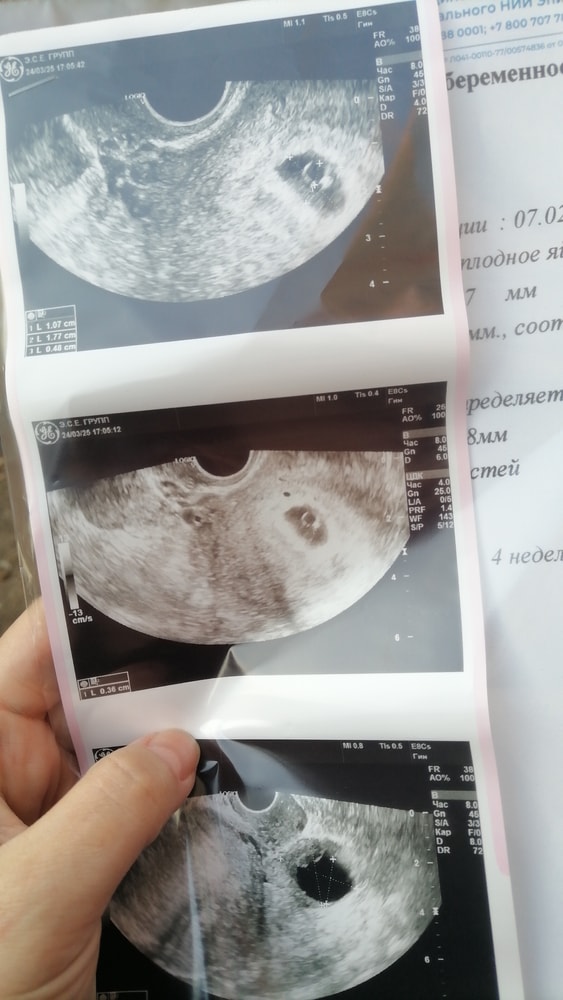

У вас уже желточный мешочек отличный, значит и эмбрион скоро появится. У меня на сроке 6+3 ктр эмбриона был 3,6мм, совсем маленький, и середечко только пульсировать начинало, через недельку или несколько дней хотя-бы, сходите ещё раз на узи, уже должен быть

вот такой точечкой эмбрион был на сроке 6+3